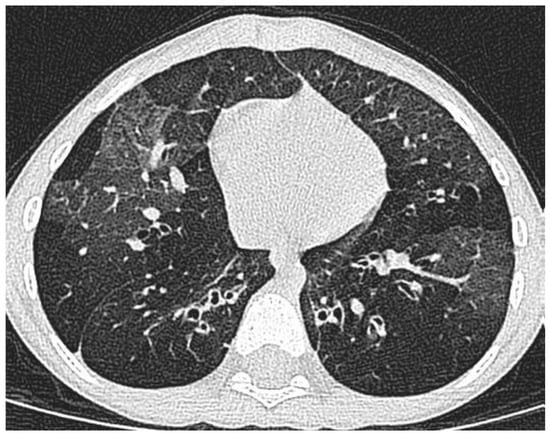

The starting point is a child referred with respiratory symptoms that do not respond to asthma therapy. The first step is a detailed history and examination, with a focussed approach to testing, to exclude other diagnoses, such as vascular ring or bronchiectasis (Figure 2). The likeliest differential diagnoses will depend on geography—airway compression by tuberculous lymph nodes is rare in London, but common in high burden areas. If it is likely that the underlying diagnosis is indeed asthma, the next step is a multi-disciplinary team assessment (Table 2).

Figure 2. Not asthma at all. There is extensive large airway thickening and dilatation, with distal air trapping. This is bronchiectasis and obliterative bronchiolitis after a severe adenovirus infection.